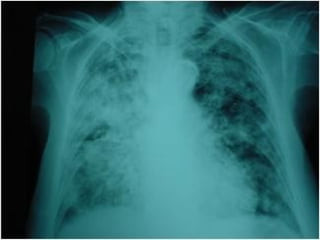

Tuberculosis pulmonar

Calcificaciones tras TBC   Caverna TBC   TBC miliar

primaria

Tuberculosis pulmonar Calcificaciones trasTBC Caverna TBC TBC miliar primaria